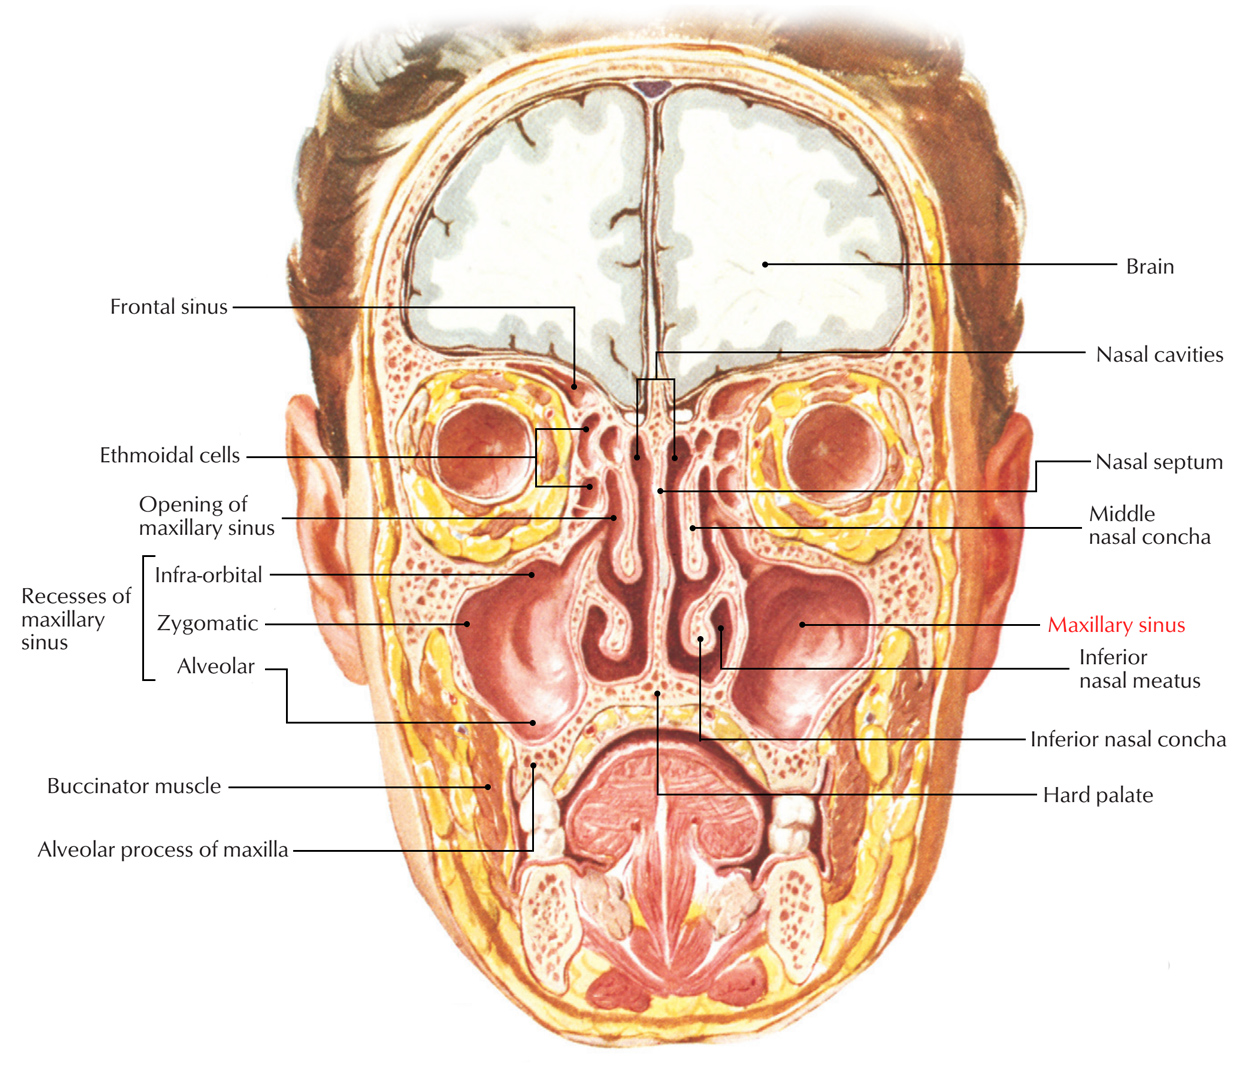

Ethmoid bone

- superior and middle Nasal concha

inferior Nasal concha

Maxillary bone

F, Z, N, L, V, E, Pl, S, INC

Alveolar bone

- Palatine process

- Alveolar process

- Maxillary tuberosity (智齒後)

Maxillary sinus

上臼齒

- Maxillary sinus下

- 大臼齒牙根分內外